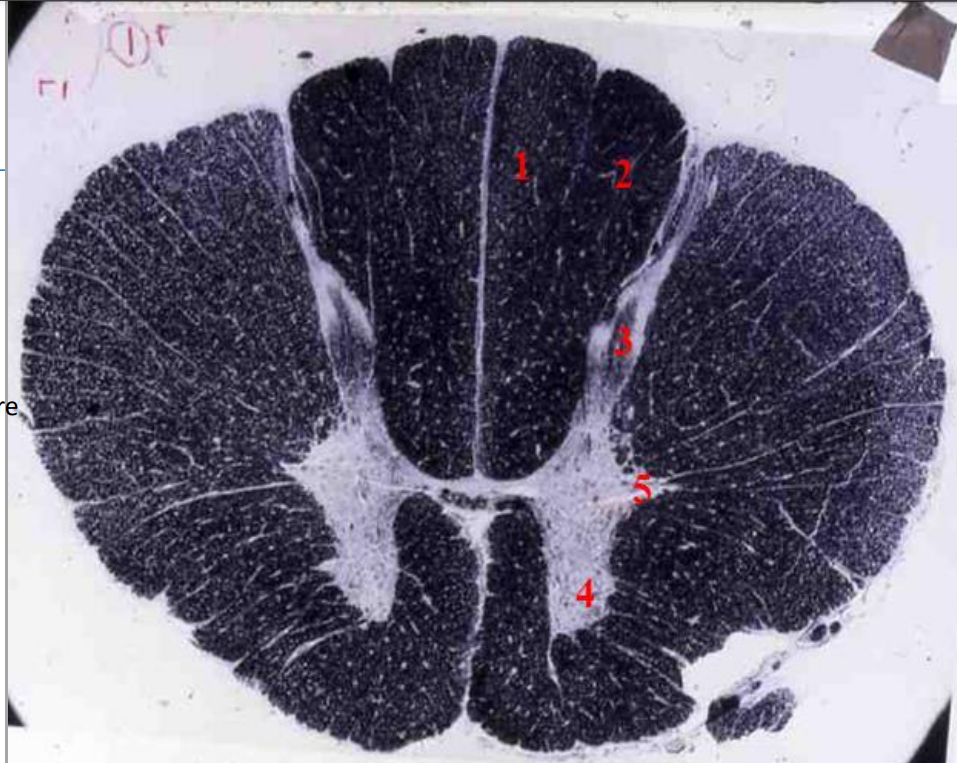

1

lumbar cord

- fibre tracts are few

- large anterior and posterior horns due to lumbar plexus

2

Q

A

fasciculus gracilis

3

posterior horn

4

anterior horn